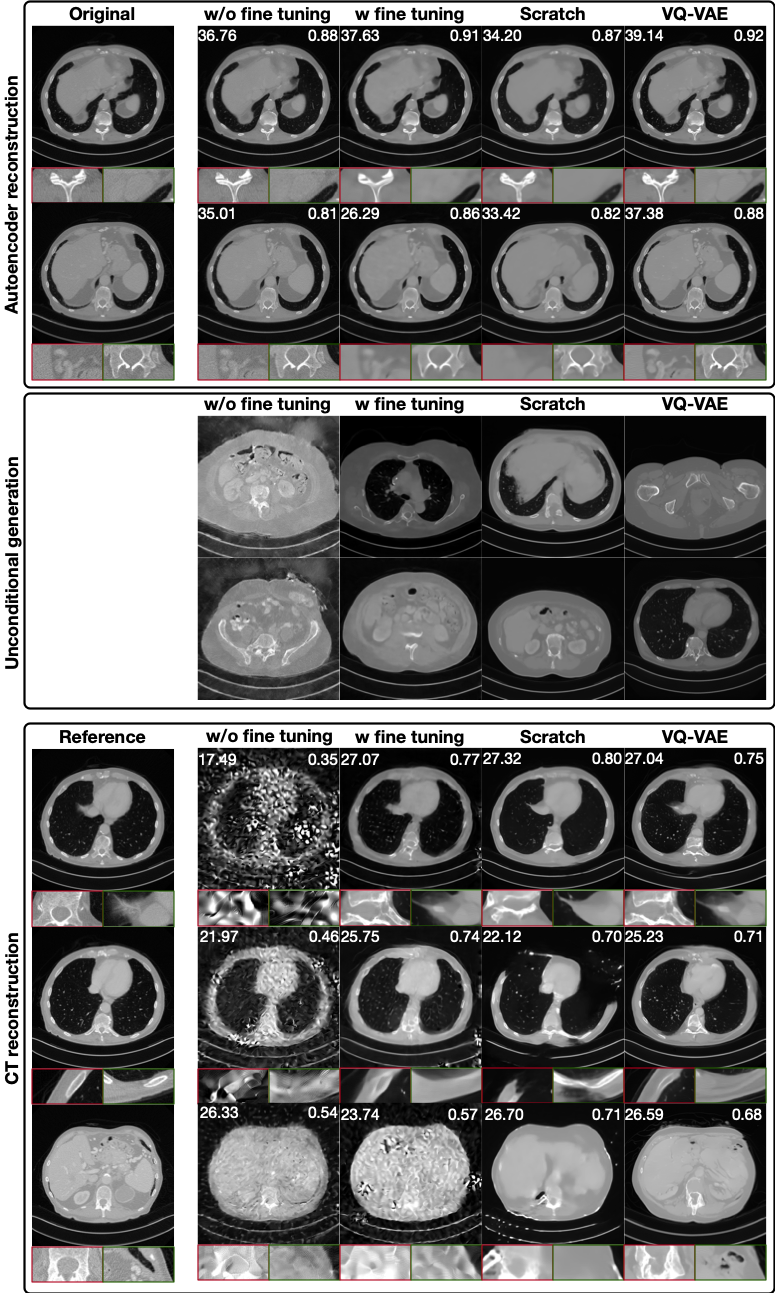

iv) 80 angles with noise and ring artifacts 50% 10000 0.05 0.25σ𝒚020.25\cdot\sigma^{2}_{\bm{y}_{0}}

v) 40 angles [0,34π\frac{3}{4}\pi) - - - -

A.7 Real-World Synchrotron CT Dataset

We acquire a high-resolution synchrotron CT dataset at a beamline operating at 24 keV with an exposure time of 4 seconds per projection. Two rock samples are scanned using parallel-beam geometry with 1200 projections over 180180^{\circ}. The detector has a pixel pitch of 9μm9\mu m and the raw projection size is 679×1653679\times 1653 pixels. Example projection images of three different scanning angles are shown in Figure 8. To remove the background area, projections are cropped to 679×768679\times 768.

Table 4: Acquisition parameters of the real-world synchrotron CT dataset used in this benchmark. Both rocks are scanned using the same setup under parallel-beam geometry.

Sample # Proj. Pixel Size (μ\mum) Exposure (s) Filter Energy (keV) # Dark Fields # Flat Fields Center (pre crop) Center (post crop) Crop Size

F3_1 (train) 1200 9 4 None 24 10 10 -61 -40.5 679×768679\times 768

F3_2 (test) 1200 9 4 None 24 10 10 -62 -41.5 679×768679\times 768

Training Reconstruction. For the training rock, flat-field correction is performed using the median of 10 dark and 10 flat fields. Log-transformation and ring artifact reduction are applied. The ring reduction method identifies anomalous detector pixels by computing the difference between the mean and median values of each detector row (Rivers, 1998; Boin & Haibel, 2006). Full-angle FBP reconstructions are used as the training target. The reconstructions of train and test rocks using full angles, median dark/flat field and ring reduction are given in Figure 9.

Normalization. The two rock samples were scanned under identical settings to align value ranges as much as possible. Nevertheless, slight inter-scan mismatches remain due to noise and mild ring artifacts. After reconstruction of the training images, we prepare the test projections. We linearly rescale its projections so that the resulting reconstructions approximately match the dynamic range of the training rock.

Benchmarking Setup. For benchmarking, the test rock is reconstructed using only 60/100/200 evenly subsampled projections (out of 1200). A flat/dark field is randomly chosen for flat field correction and no ring artifact correction is applied.

Refer to caption

Figure 8: Example projection images (before cropping) of the synchrotron dataset at different angles.

Figure 9: Reference reconstructions of three slices from the training and test rocks using all 1200 angles.